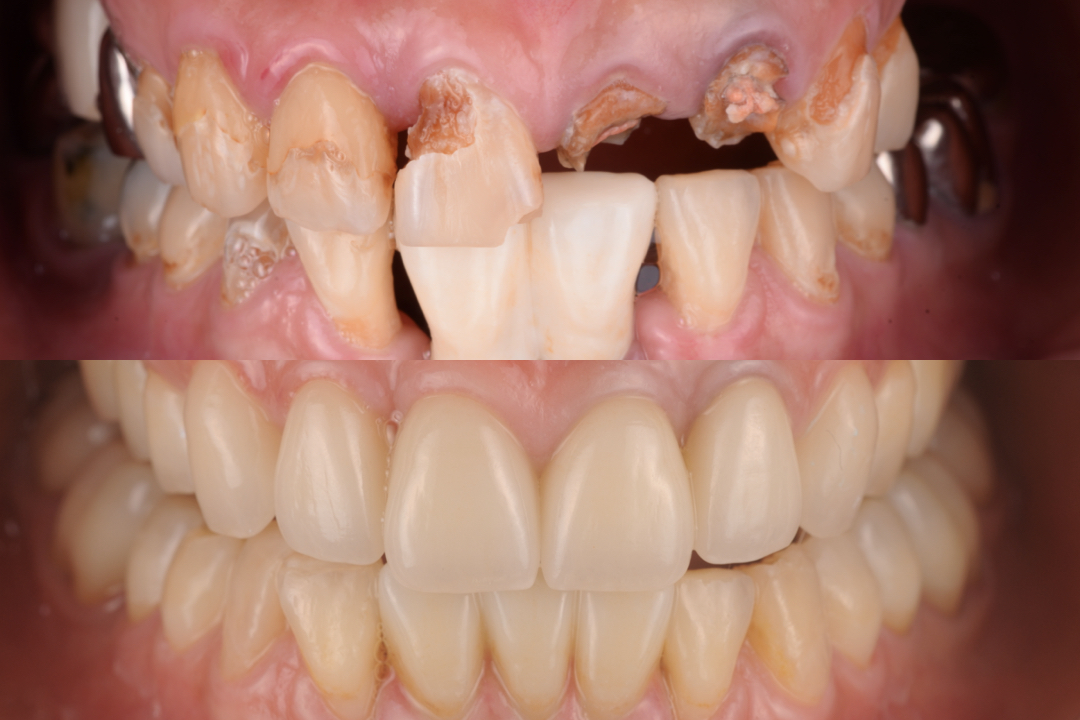

【担当医;荻原太郎】全体的な治療、審美治療、イ...